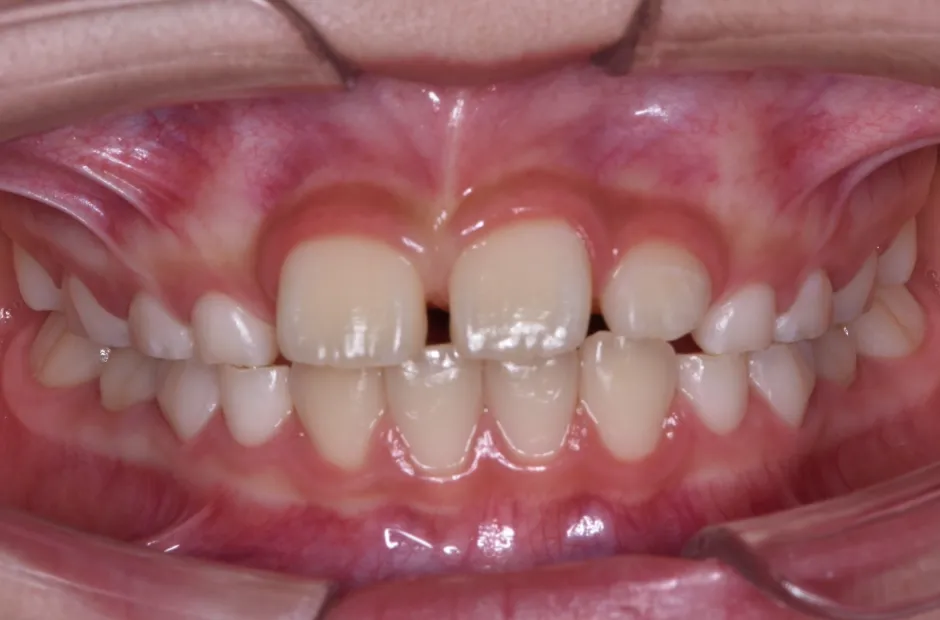

治療症例

ブラケット矯正

前歯部反対咬合

| 診断名・主訴 | 前歯部反対咬合 |

|---|---|

| 年齢・性別 | 14歳・男性 |

| 治療期間・回数 | 1年2か月 |

| 治療に用いた主な装置 | ブラケット矯正 |

| 抜歯部位 | なし |

| 治療費 | 60万円(税抜) |

| リスク・副作用 | 装置による違和感・疼痛・歯肉退縮・歯根吸収・虫歯のリスクなど |

治療前

治療後